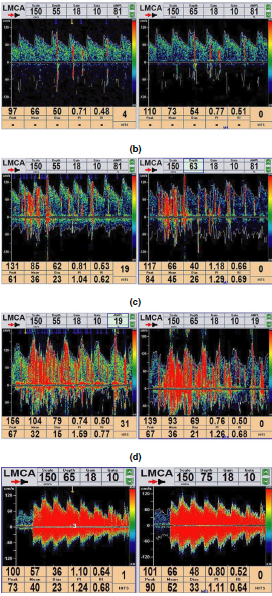

Methods: In this study, we enrolled consecutive migraineurs who underwent a structured,standardized questionnaire for family and personal history and for detailed migraine features. RLS was diagnosed based on a contrast enhancement transcranial Doppler (c-TCD) examination.

Results: Overall, 113 migraine with aura (MA) and 192 migraine without aura (MO) patients were included. Patients with MA and RLS (MARLS+) had a higher frequency for sensory aura symptoms than those with MA without RLS (MARLS?) (27.4% vs.10.0%, p = .03). Patients with MO and RLS (MORLS+) presented with significantly

younger initial age of migraine onset and experienced more severe pain intensity than those with MO without RLS (MORLS?) (mean ± SD, 25.6 ± 8.9 vs. 29.8 ± 12.7 years,p = .008 and 5.9 ± 1.4 vs. 5.3 ± 1.3, p = .006, respectively). There was no relationship between the degree of shunt and the clinical parameters of headache.

Conclusions: Our results indicate that MO patients presented with a younger initial age of migraine onset and that sensory aura symptoms in MA patients may predict the presence of RLS. However, we did not find support for relationship between the

degree of shunt and clinical parameters of headache.